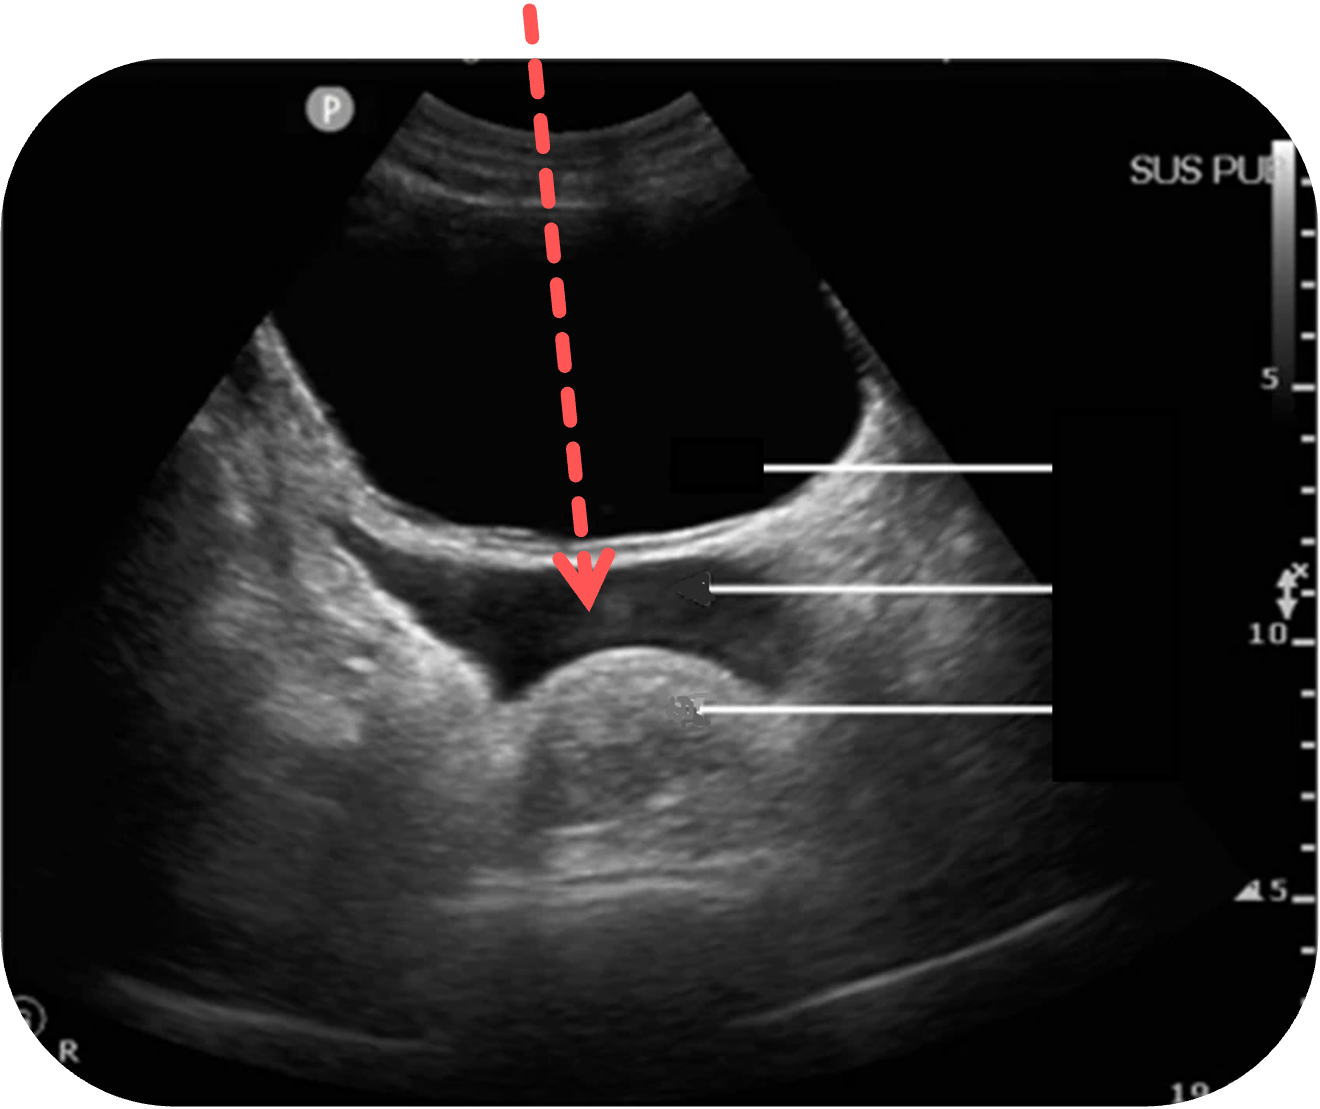

Freie Flüssigkeit beim Mann

Freie Flüssigkeit im Proust-Raum (Excavatio rectovesicalis) beim Mann ist immer als pathologisch zu werten und erfordert in nahezu jedem Fall eine weitergehende Diagnostik.

In der Sonographie zeigt sich freie Flüssigkeit typischerweise als anechogene oder echoarme Zone zwischen Harnblase und Rektum

In Abhängigkeit von der Zusammensetzung kann die Flüssigkeit auch inhomogene oder echoreiche Anteile aufweisen, etwa bei Blutungen oder infektiösem Exsudat

Figure 3 aus Fasseaux, A., Pès, P., Steenebruggen, F. et al. Are seminal vesicles a potential pitfall during pelvic exploration using point-of-care ultrasound (POCUS)?. Ultrasound J 13, 14 (2021). https://doi.org/10.1186/s13089-021-00209-7. Es wurden teilweise die Markierungen und Beschriftungen ergänzt.

Der Proust-Raum ist der tiefste intraperitoneale

Zu den häufigsten Ursachen zählen intraabdominelle Traumata mit Blutungen (z. B. Leber